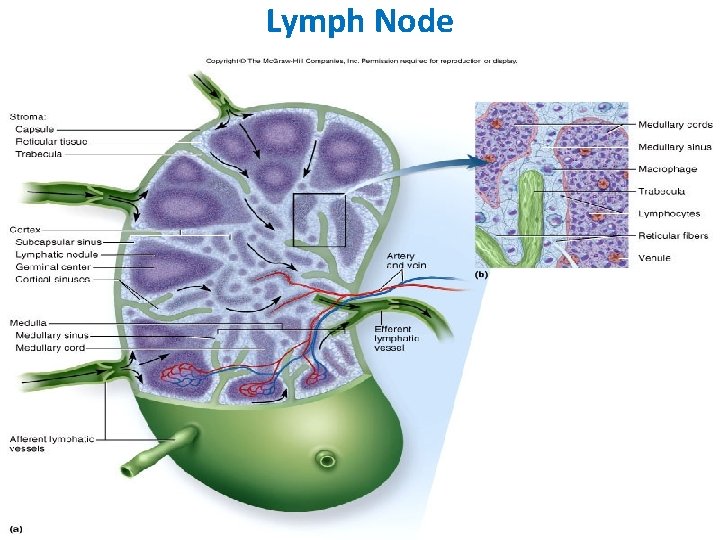

Lymph Node • • • Capsulated Afferent lymphatics “subcapsular sinus” Hilum – blood vessels, efferent lymphatic Cortex and medulla Cortex – Lymphatic nodules, germinal centres – “Paracortex” T-dependent zone • Medulla – Medullary cords and sinusoids M C

LYMPH NODES These are the smallest but most numerous encapsulated lymphoid organs. Scattered in groups along lymphatic vessels , they act as in-line filters of the lymph, removing antigens and cellular debris and adding Igs. Lymph nodes are bean-shaped structures with convex and concave surfaces. The parenchyma consists of a peripheral cortex, adjacent to the convex surface, and a central medulla lying near the depression (hilum) in the concave surface. The connective tissue capsule gives off trabeculae that penetrate between the cortical nodules and subdivide the cortex. Cortex. The cortex is dark-staining owing to the presence of tightly packed lymphocytes. These are suspended in a reticular connective tissue network and arranged as a layer of typical secondary lymphoid nodules (containing primarily B lymphocytes) with germinal centers. The cortex also contains reticular cells, antigen-presenting follicular dendritic cells, macrophages, a few plasma cells, and some helper T cells.

Medulla. Lighter staining than the cortex, the medulla is composed of cords of lymphoid tissue (medullary cords) separated by medullary sinuses. The lymphocytes are mainly small, less numerous than in the cortex. The cords are also rich in reticular cells and fibers and contain many plasma cells that have migrated from the cortex. Paracortical zone. This is the T-dependent region, lying between the cortical lymphoid nodules and the medulla. It contains mainly T lymphocytes suspended in a reticular connective tissue. B lymphocytes, plasma cells, macrophages, and antigen-presenting interdigitating dendritic cells may also be present. Lymphatic vessels. Sinuses (subcapsular, peritrabecular, medullary). Functions: 1. Filtration of lymph 2. Lymphocyte production (lymphopoiesis). 3. Immunoglobulin production.